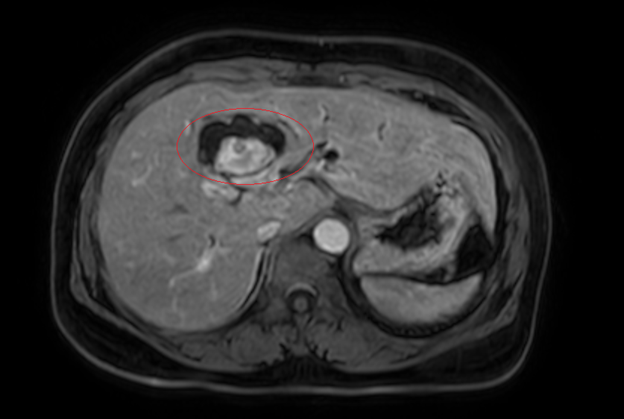

Hình ảnh giãn khu trú đường mật gan trái, tạo cấu trúc dạng nang và sỏi đường mật bên trong (vòng tròn đỏ), chèn ép kèm giãn đường mật trong gan hai bên trên phim chụp MRI - Ảnh BVCC